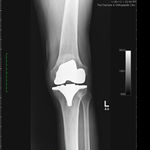

Patient seen with Bilateral Knee Pain and had been unable to walk for two (2) years.

On clinical and radiological examination, he was assessed as having Severe Primary Osteoarthritis of both knees.

Bilateral Total Knee Replacement was recommended, and performed on July 27th 2011. Since surgery, the patient has made good progress and can now mobilize with the aid of a walker.

His x-rays and clinical examination suggest good early outcome with a fully mobilized patient with pain free knees and the ability to walk independently.